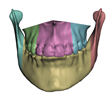

- In maxillary procedures, the maxilla is separated from the skull through a Lefort osteotomy, classified based on its anatomical level. In this cohort, the distribution of cases is: 8 Lefort I cases and 1 Lefort II case; one patient did not undergo maxillary surgery. Moreover, after a Lefort I osteotomy, the maxilla may be segmented (typically into three fragments) in order to expand the upper arch. Maxilla segmentation was applied to 6 patients in this cohort.

- In mandibular procedures, the mandible may be sagittally split on both rami (bilateral sagittal split osteotomy, BSSO) or only one ramus (unilateral sagittal split osteotomy, USSO). In this cohort, the distribution of cases is: 7 BSSO cases, 1 USSO case; two patients did not undergo mandibular surgery. Additionally, a chin osteotomy or genioplasty may be also performed. Genioplasty was applied to 1 patient in this cohort.